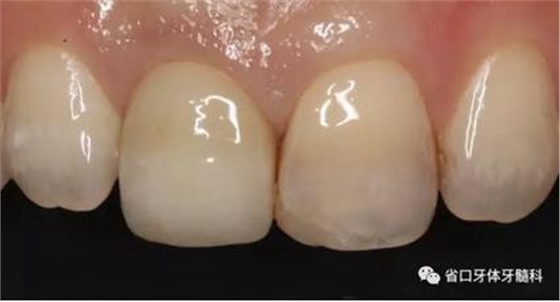

(4)最終修復(fù)與隨訪:經(jīng)過3個月左右的塑形,上頜右側(cè)中切牙臨時修復(fù)固位良好,菌斑控制良好,近遠(yuǎn)中齦乳頭充盈良好,齦緣水平及形態(tài)與 鄰牙相對稱。牙齦塑形穩(wěn)定后,以臨時修復(fù)體制作個性化轉(zhuǎn)移桿并取模轉(zhuǎn)移,并以原廠氧化鋯基臺制備個性化基臺及全瓷冠。正確就位最終基臺,加 力30N·cm。制備粘接代型,去除多余粘接劑,以Unicem粘接固位上頜右側(cè)中切牙全瓷修復(fù)體。固化穩(wěn)定后,再次確定咬合無干擾。最終修復(fù)完成后 隨訪3個月及6個月,上頜右側(cè)中切牙種植修復(fù)固位穩(wěn)定,近遠(yuǎn)中齦乳頭充 盈良好,唇側(cè)齦緣水平穩(wěn)定。

圖34 負(fù)重3個月后

圖35 負(fù)重6個月后復(fù)診

上頜右側(cè)中切牙修復(fù)體固位良好,牙齦乳頭充盈良好,齦緣水平對稱 修復(fù)體與對側(cè)同名牙協(xié)調(diào)一致。外觀笑容美觀協(xié)調(diào)?;颊邼M意。X線檢查示 上頜右側(cè)中切牙種植體周穩(wěn)定骨質(zhì)包繞,唇側(cè)骨板>2mm,相鄰牙槽骨高度穩(wěn)定,基臺及修復(fù)體就位良好。分別根據(jù)Furhauser的PES和Bulser的WES 進(jìn)行美學(xué)評分,總分值為20,美學(xué)效果良好。